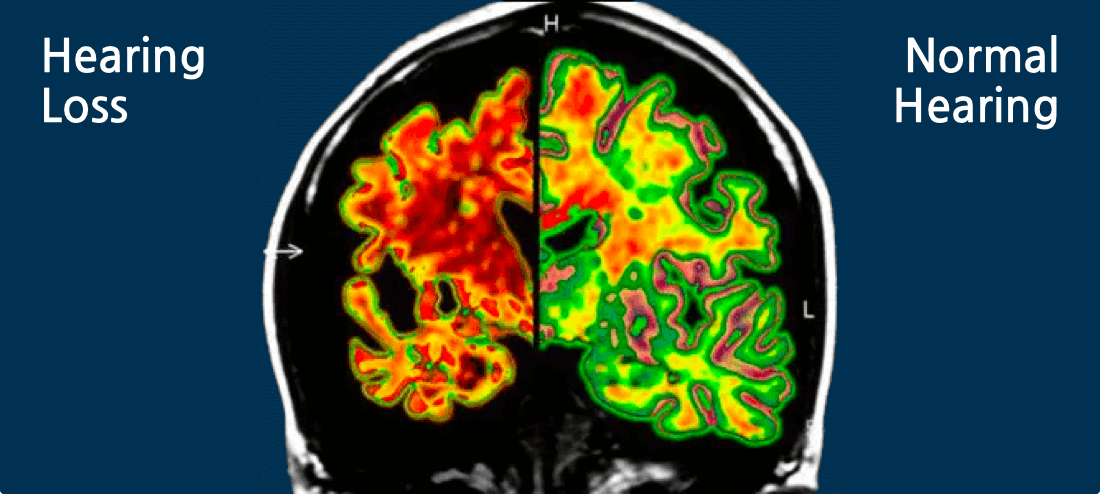

Improving hearing loss will decrease your risk of dementia and alzheimer’s.

Address Hearing Loss To Protect Cognitive Abilities

We are passionate about treating hearing loss because it’s a critical part of long-term health and well-being. Untreated hearing loss can lead to a number of health issues, so early intervention is key. Hearing loss and tinnitus are so related to cognitive decline, nothing is more rewarding to us than helping decrease a patient’s risk of dementia and Alzheimer’s through hearing treatment.